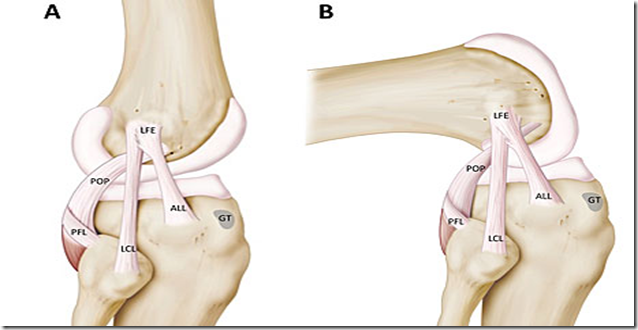

Agora, trabalhando com base em estudos de outros cientistas, os médicos belgas dizem ter conseguido mapear o ligamento, que vai do lado mais externo do osso da coxa (fêmur) para a tíbia.

Há quatro ligamentos principais no joelho, se cruzando entre o fêmur e a tíbia para garantir a estabilidade e evitar movimentos excessivos de nossos membros.

Os médicos belgas usaram técnicas de dissecação microscópica para examinar 41 joelhos e conseguiram identificar o ligamento em 40 amostras.